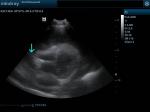

Αυτό μας καθοδήγησε πως πιθανόν ο ασκίτης να οφείλεται σε ανεπάρκεια της τριγλώχινης βαλβίδας της δεξιάς καρδιάς. Στον έλεγχο της καρδιάς διαγνώστηκε περικαρδιακή συλλογή με καρδιακό επιπωματισμό, και μία μάζα η οποία εντοπιζόταν στον δεξιό κόλπο.

(πράσινο βέλος περικάρδιο, μπλέ βέλος περικαρδιακή συλλογή)